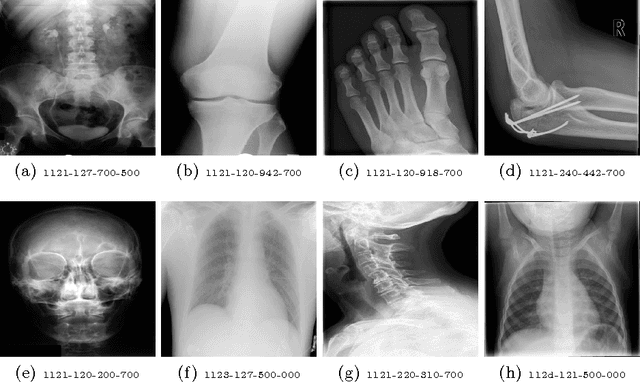

Abstract:Medical images can be a valuable resource for reliable information to support medical diagnosis. However, the large volume of medical images makes it challenging to retrieve relevant information given a particular scenario. To solve this challenge, content-based image retrieval (CBIR) attempts to characterize images (or image regions) with invariant content information in order to facilitate image search. This work presents a feature extraction technique for medical images using stacked autoencoders, which encode images to binary vectors. The technique is applied to the IRMA dataset, a collection of 14,410 x-ray images in order to demonstrate the ability of autoencoders to retrieve similar x-rays given test queries. Using IRMA dataset as a benchmark, it was found that stacked autoencoders gave excellent results with a retrieval error of 376 for 1,733 test images with a compression of 74.61%.